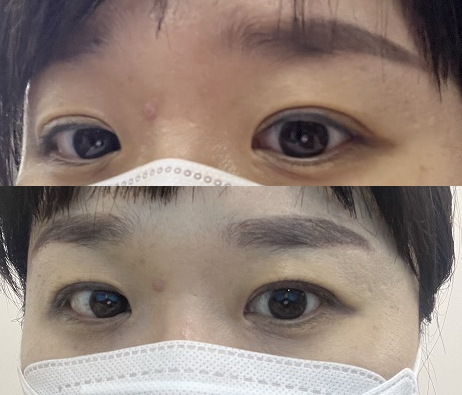

2022년 2월 15일 화요일

오전 9시 출근해서 찍은 사진

다 지워졌나 봐 wwwwwwwww

멍도 많이 빠지고 붓기는 다 빠졌나봐.. 그래서 홀딩 취소하고 밤에는 운동 갔다오…

즐거우니까 어플 셀카로 굉장히 만족하고 있습니다www